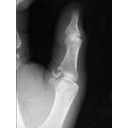

Xray.jpg